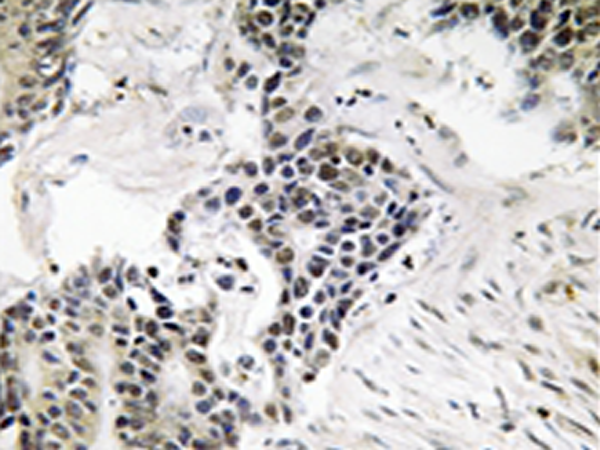

IHC |

IHC positive control: |

Human colon carcinoma tissue |

IHC Recommend dilution: |

50-100 |